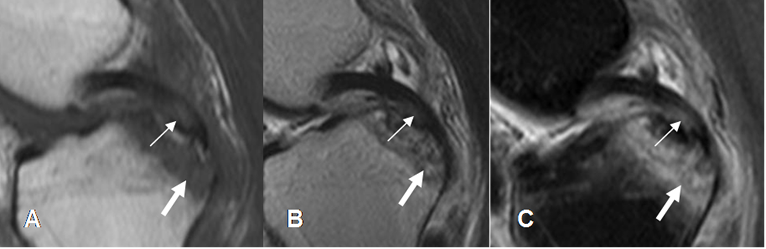

Fig 112. Esguince grado II del LCP.

A: RM sagital en T1, B: RM sagital en T2 y C: RM sagital en STIR. Zona de aumento en la señal en el tercio distal del LCP, con ruptura de algunas fibras por esguince GII. (Flecha delgada). Además hay contusión en la parte posterior de La tibia. (Flecha gruesa).